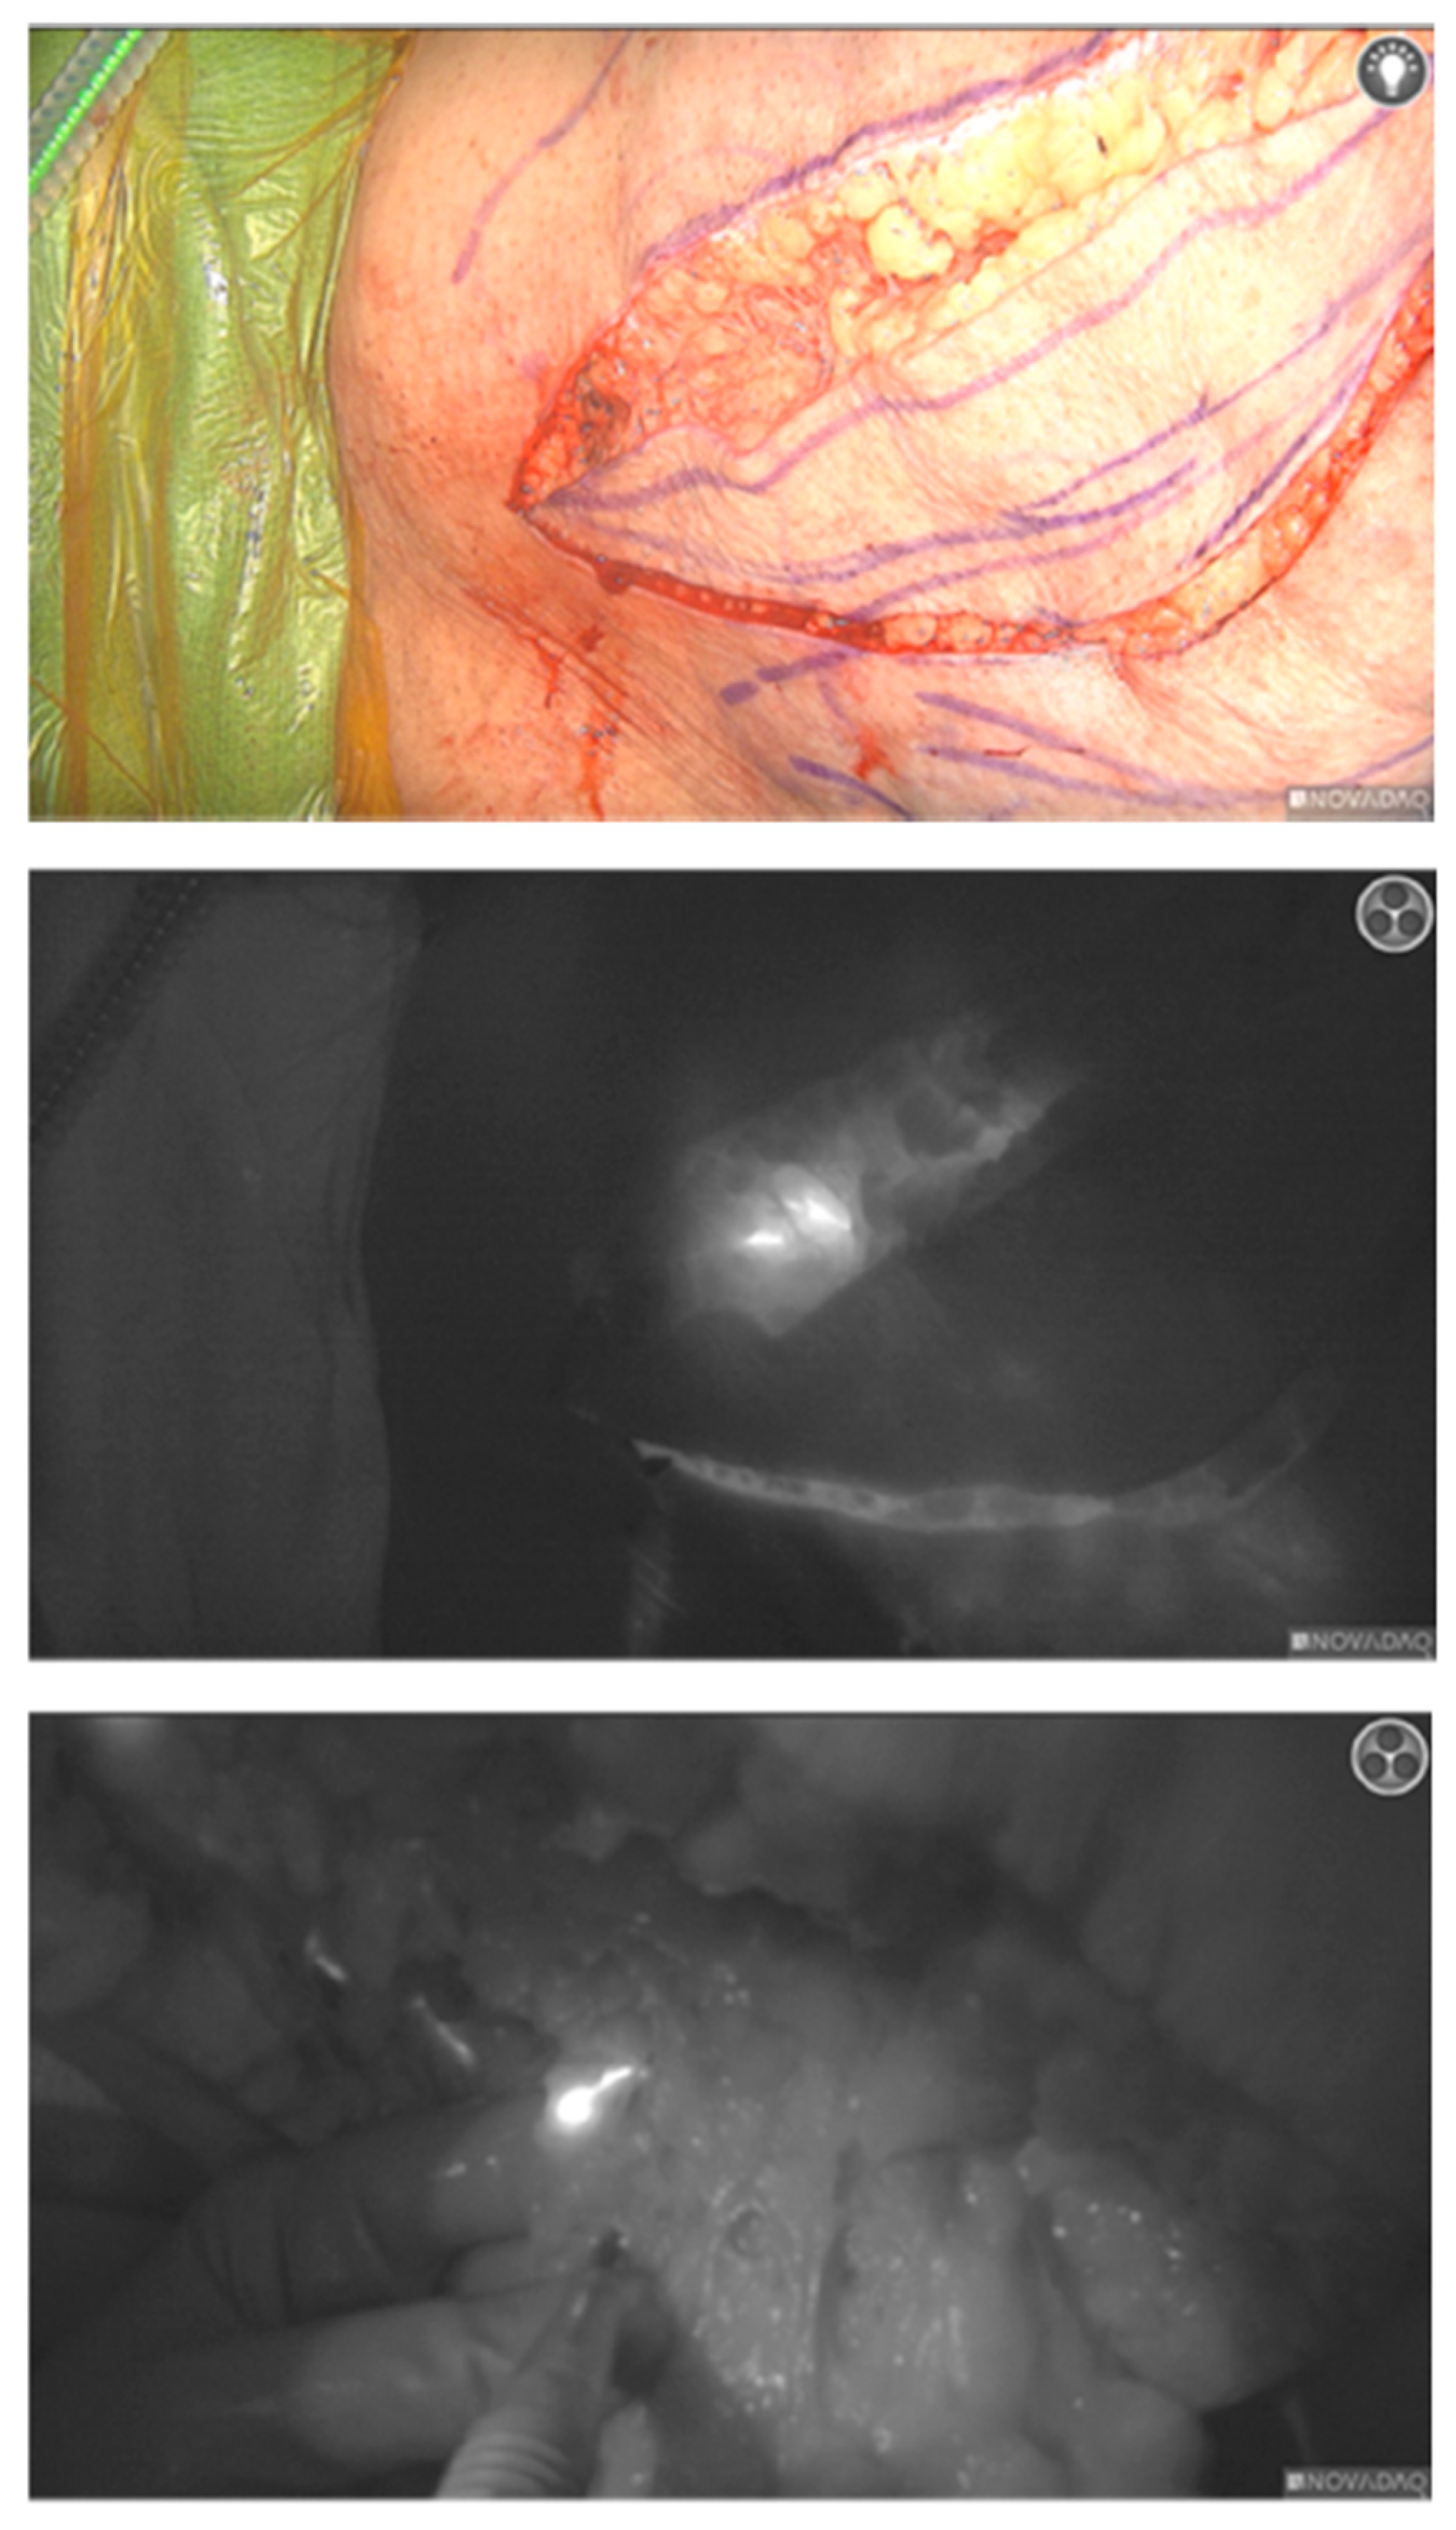

2.2. Procedure